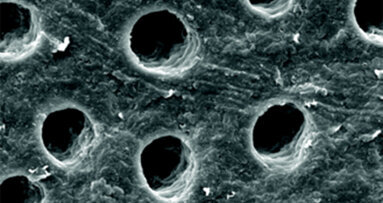

V naší klinické praxi byla hypersenzitivita dentinu (HD) vždy výzvou. Nejlepším přístupem pro nás doposud bylo navrhnout domácí řešení, ...